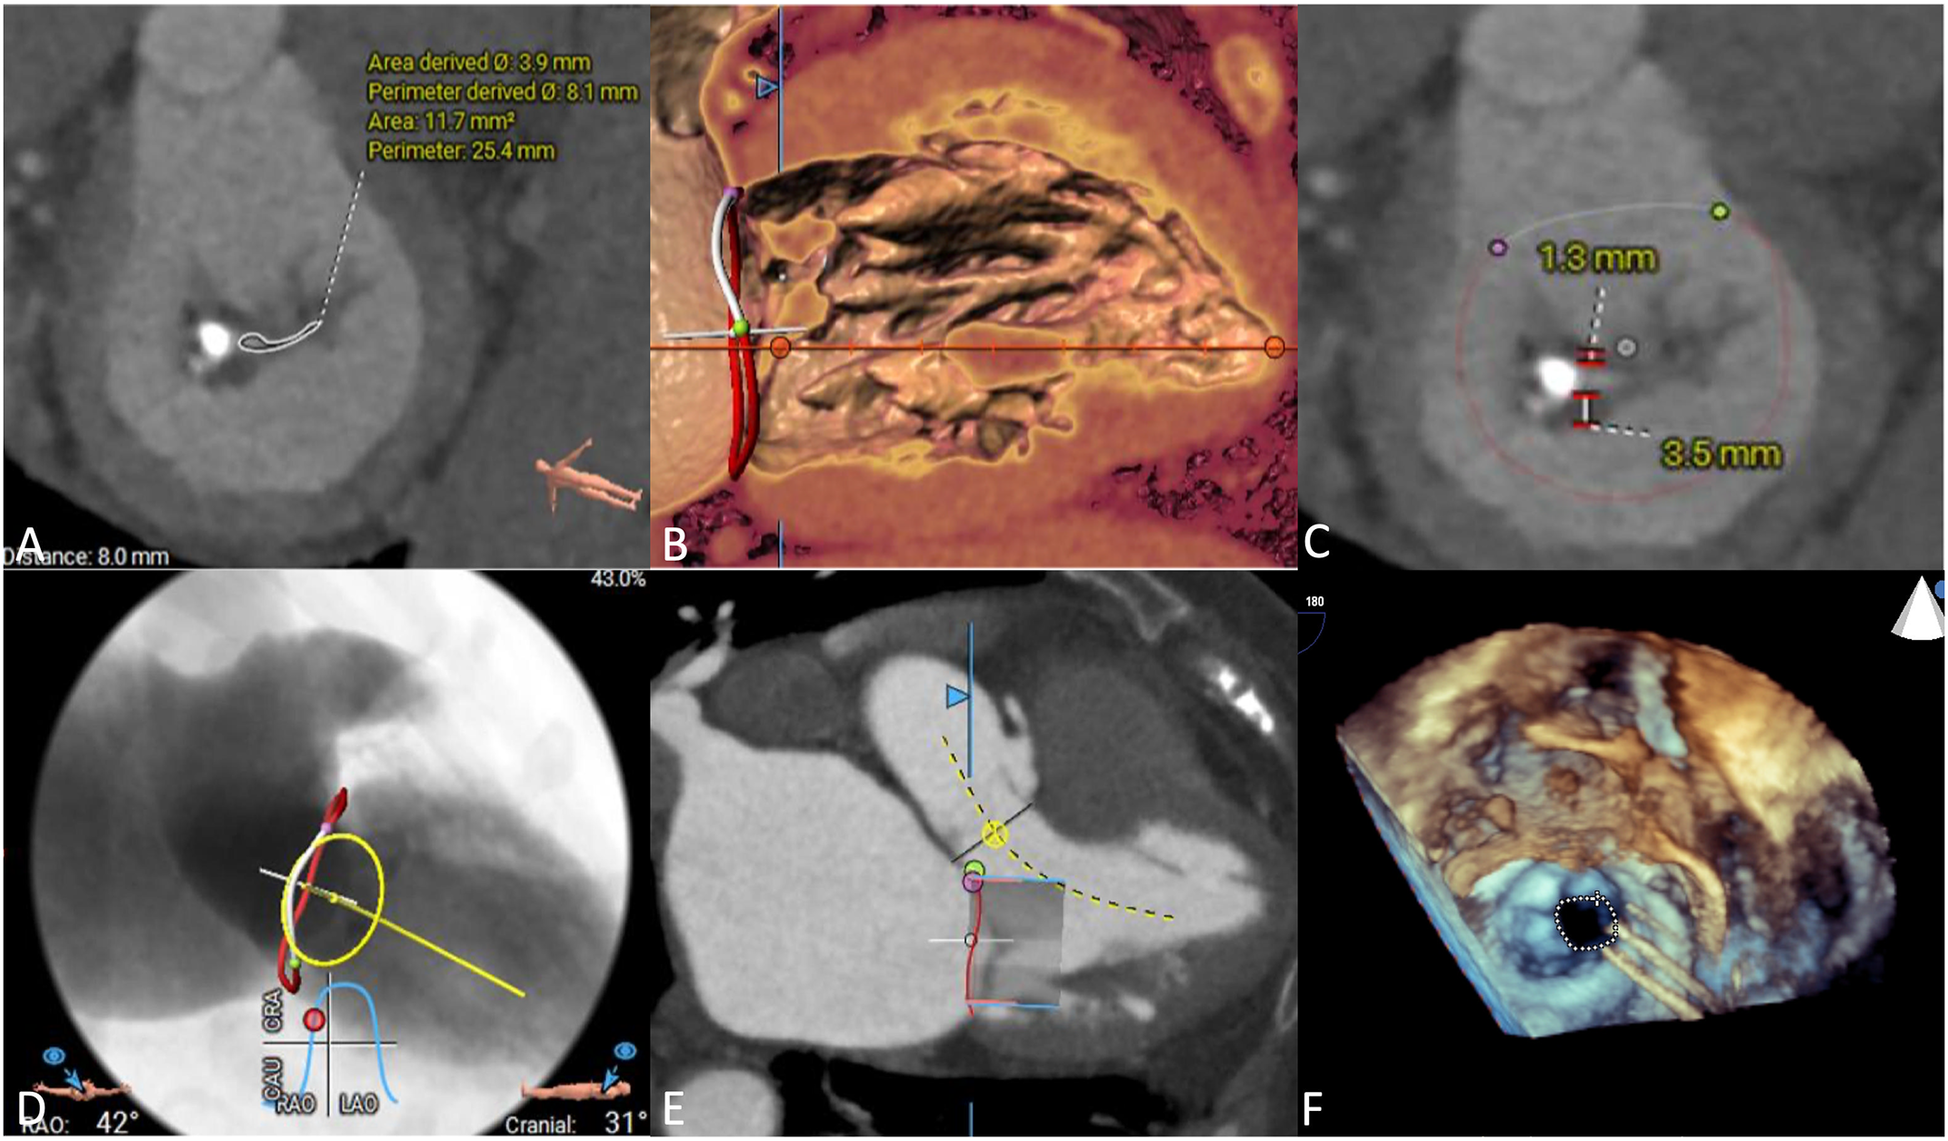

We used CTA to evaluate MV anatomy before the procedures, including evaluation of the mitral annulus, leaflets, left ventricular outflow tract and subvalvular apparatus (Figures 2A–E). Coronary angiography was used to rule out severe coronary artery disease. All patients underwent preprocedural TTE to assess MV and right cardiac system functions (Figure 2F). After assessing each patient's age, frailty, comorbidities, and surgical risk, the cardiac team recommended that all patients undergo TMVR.

Figure 2

Preprocedural imaging assessments. (A) Mitral annulus measurement, the annular area was 11.7 mm2. (B) Subvalvular apparatus evaluation, chordae tendinae was shown thickened. (C) Leaflets of mitral valve evaluation. (D) Implanted projection angle determination. (E) Neo-left ventricular outflow tract prediction. (F) Rheumatic mitral stenosis was displayed in preprocedural echocardiography.